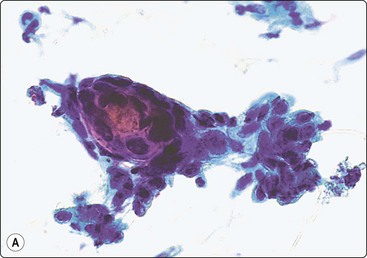

A 60-year-old woman with a history of right mastectomy for cancer 4 years previously presented with a lump in the right axilla. It was described as subcutaneous by the surgeon who performed the FNB and the clinical diagnosis was metastasis of breast cancer. Smears were highly cellular, of epithelial cells both forming cohesive aggregates and dispersed as single cells. True papillary fragments were not seen. The cells had a moderate amount of dense cytoplasm and there was relatively mild nuclear atypia (Fig. 14.10). The pattern was considered to be in keeping with metastasis of a low-grade breast carcinoma. However, the nodule was, in fact, intracutaneous and the histology was reported as syringocystadenoma papilliferum (Fig. 14.10).36

image image image

Fig. 14.10 Syringocystadenoma papilliferum

Clustered and dispersed epithelial cells; moderate amount of cytoplasm; mildly atypical nuclei; no true papillary fragments (A, MGG, HP; B, H&E, IP); (C) Corresponding tissue section (H&E, LP).